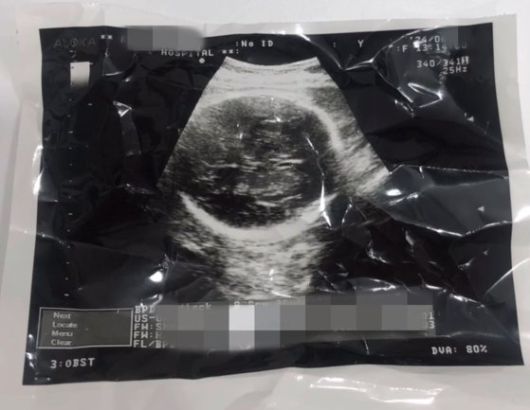

36주차 낙태 의혹이 불거진 영상 관련 태아 초음파 사진 캡처. 사진 인스타그램 |

경찰은 영상에 담긴 태아 초음파 사진도 중요한 단서로 봤다. 초음파 사진에서 촬영 날짜와 출산 예정일 등 의료 정보를 확인하고, 산부인과 의사 등에 대한 참고인 조사를 진행해 A씨 본인 주장과 같이 임신 36주차에 해당한다고 봤다. 영상에선 산부인과 관계자로 추정되는 한 여성이 “이 정도면 (아이를) 낳아야 한다. 심장이 잘 뛰고 있다”고 언급하기도 한다.